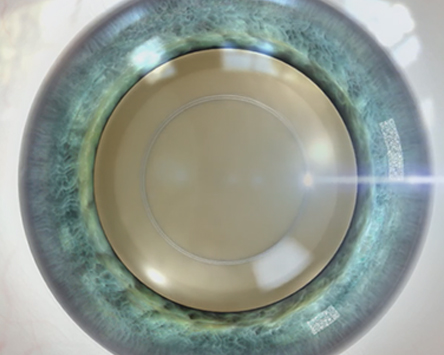

수정체낭 절개

수정체 전낭 절개시 완벽한 원이

완벽한 시력 결과를 낳습니다.

올레이저 노안백내장

정확하고 매끄러운

레이저 절개